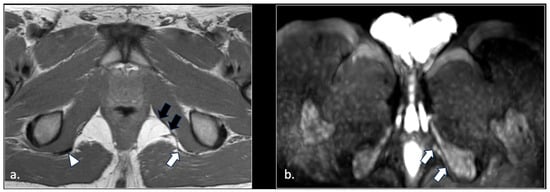

MRI in Chronic Pudendal Neuralgia: Diagnostic Criteria and Associated Pathologies

by Michele Gaeta, Sofia Turturici, Karol Galletta, Carmelo Geremia, Attilio Tuscano, Aurelio Gaeta, Marco Cavallaro, Salvatore Silipigni and Francesca Granata

Diagnostics 2026, 16(2), 326; https://doi.org/10.3390/diagnostics16020326 (registering DOI) - 20 Jan 2026

Background/Objectives: Chronic pudendal neuralgia is a relatively rare condition in the general population, with an incidence of 1%. Although diagnosis of pudendal neuralgia is mainly clinical, Magnetic Resonance Imaging (MRI) is commonly performed to obtain further information. However, clear criteria and guidelines for MRI diagnosis and the clinical–radiological correlation are still not definite. Methods: We reviewed 81 patients with chronic pudendal neuralgia, studied by an MRI designed protocol for a pelvis and pelvic floor examination. A key element of the protocol was the use of a diffusion-weighted imaging (DWI) technique with echo planar imaging (EPI) sequence (b-values of 0, 100, and 600) for the neurographic evaluation of the nerve. Results: MRI examination revealed DWI abnormalities in 42/81 patients. Pudendal nerve abnormalities were unilateral in 33/42 patients and bilateral in 9/42. Moreover, in 23/42 patients, pathologies related to a high probability of neuropathy have been identified. Conclusions: This study highlights the role of pelvic MRI as a valuable imaging modality in the evaluation of patients with chronic pudendal neuralgia. In the study protocol we propose, an essential role is played by the DWI technique, which improves the visual definition of the pudendal nerve and related anatomical structures. By focusing on anatomical visualization and structured image interpretation, our work provides a practical imaging-oriented contribution to a field in which standardized MRI evaluation is still lacking. Full article